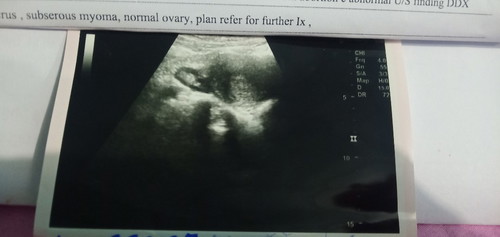

แห้วอีกแล้วท้องไม่เคยสำเร็จสักทีขอกำลังใจหน่อยค่ะ

ครรภ์นี้เป็นครรภ์ที่2ของปีนี้ พรุ่งนี้เตรียมแอดมิด